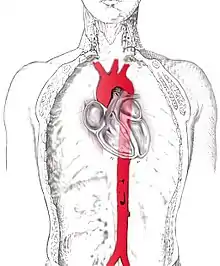

аорта

- (Anatomie) Aorte.

- (Anatomie) Aorte.

- (Anatomie) Aorte.